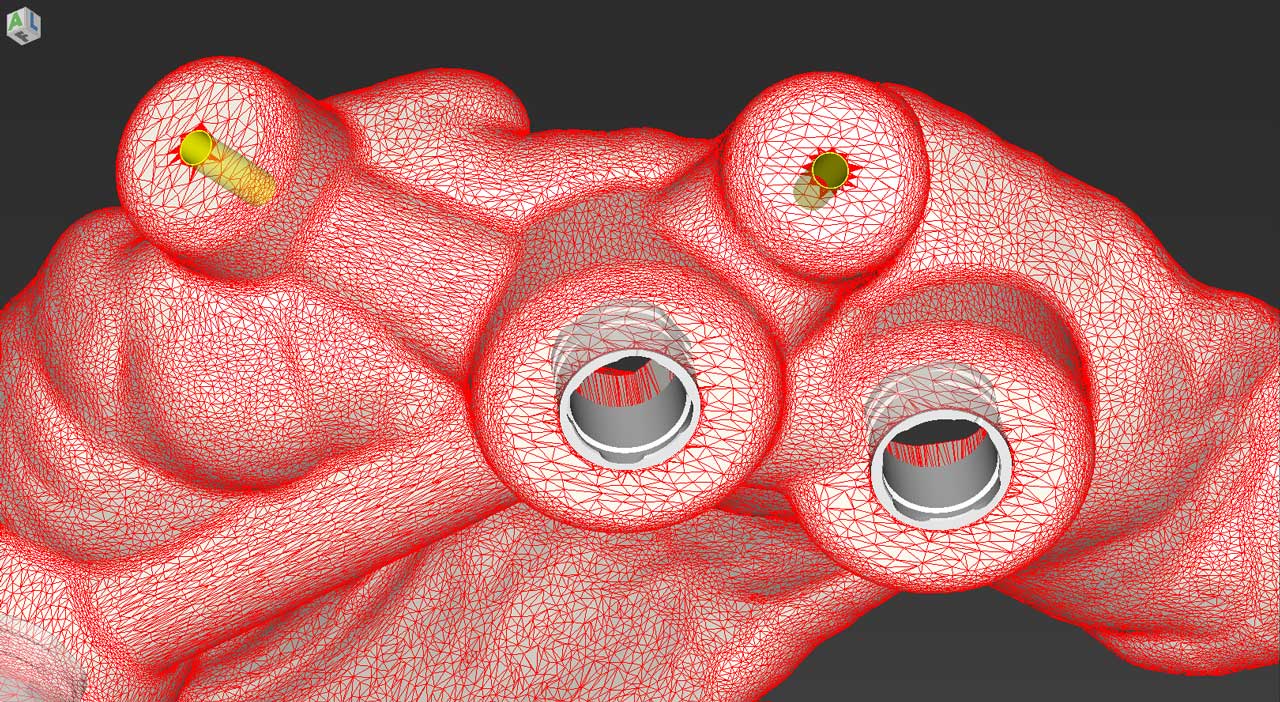

Σχεδιασμός χειρουργικού οδηγού

Κατασκευή χειρουργικού οδηγού στο ιατρείο (3d printing)

Πρακτική άσκηση: ο κάθε συμμετέχων θα σχεδιάσει σε ειδικό λογισμικό έναν χειρουργικό οδηγό